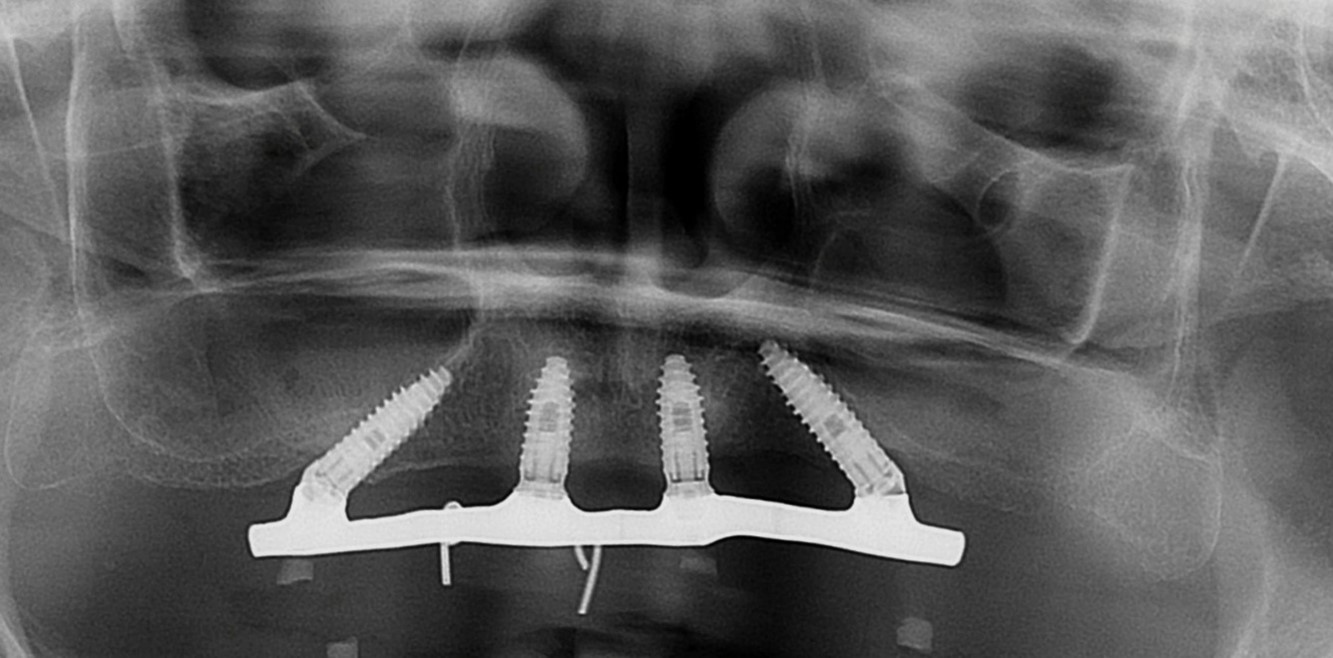

Na análise radiográfica, constatou-se pneumatização do seio maxilar direito em direção ao pilar canino. No lado esquerdo, a extensão da pneumatização poderia inviabilizar a realização da técnica sem enxertos ósseos. Para garantir a instalação precisa e segura do implante, foi realizado um acesso lateral à janela do seio maxilar, permitindo o tratamento da parede anterior do seio com uma sonda para determinar a posição ideal do implante distal. Aproveitou-se o máximo de osso disponível, tangenciando o seio maxilar e eliminando a necessidade de enxertos ósseos. Foi escolhido o sistema Vezza da FGM, devido a geometria que fornece alta estabilidade primária e oferece conexão hexagonal externa universal, ou seja, bastante versátil.

Após a perfuração inicial com broca lança de 15 mm para os implantes distais e 11 mm para os anteriores, a perfuração com broca 2,4 nos mesmos comprimentos. paralelizadores foram utilizados para verificar o polígono formado e a posição dos implantes. A perfuração seguinte com broca 3.4 e, após, com broca 3.9, a onde foi realizado subperfuração em comprimento (50%), garantindo melhor estabilidade primária. Foram instalados implantes Vezza de 4,3×15 mm na região posterior da maxila e de 4,3×11 mm na região anterior.

Todos os implantes atingiram um torque de 80 N, possibilitando a realização de carga imediata. Mini pilares retos com transmucoso de 2mm foram instalados nos implantes anteriores e mini pilares angulados de 30 graus com transmucoso de 3mm nos distais, corrigindo a ajuste dos implantes e sustentando o assentamento passivo da barra.

Fig. 2 – Radiografia inicial

FIG. 12 – Radiografia de acompanhamento de 17 meses após a cirurgia.

FIG. 14a b c d – Radiografia de acompanhamento de 26 meses após a cirurgia. (implante 11)